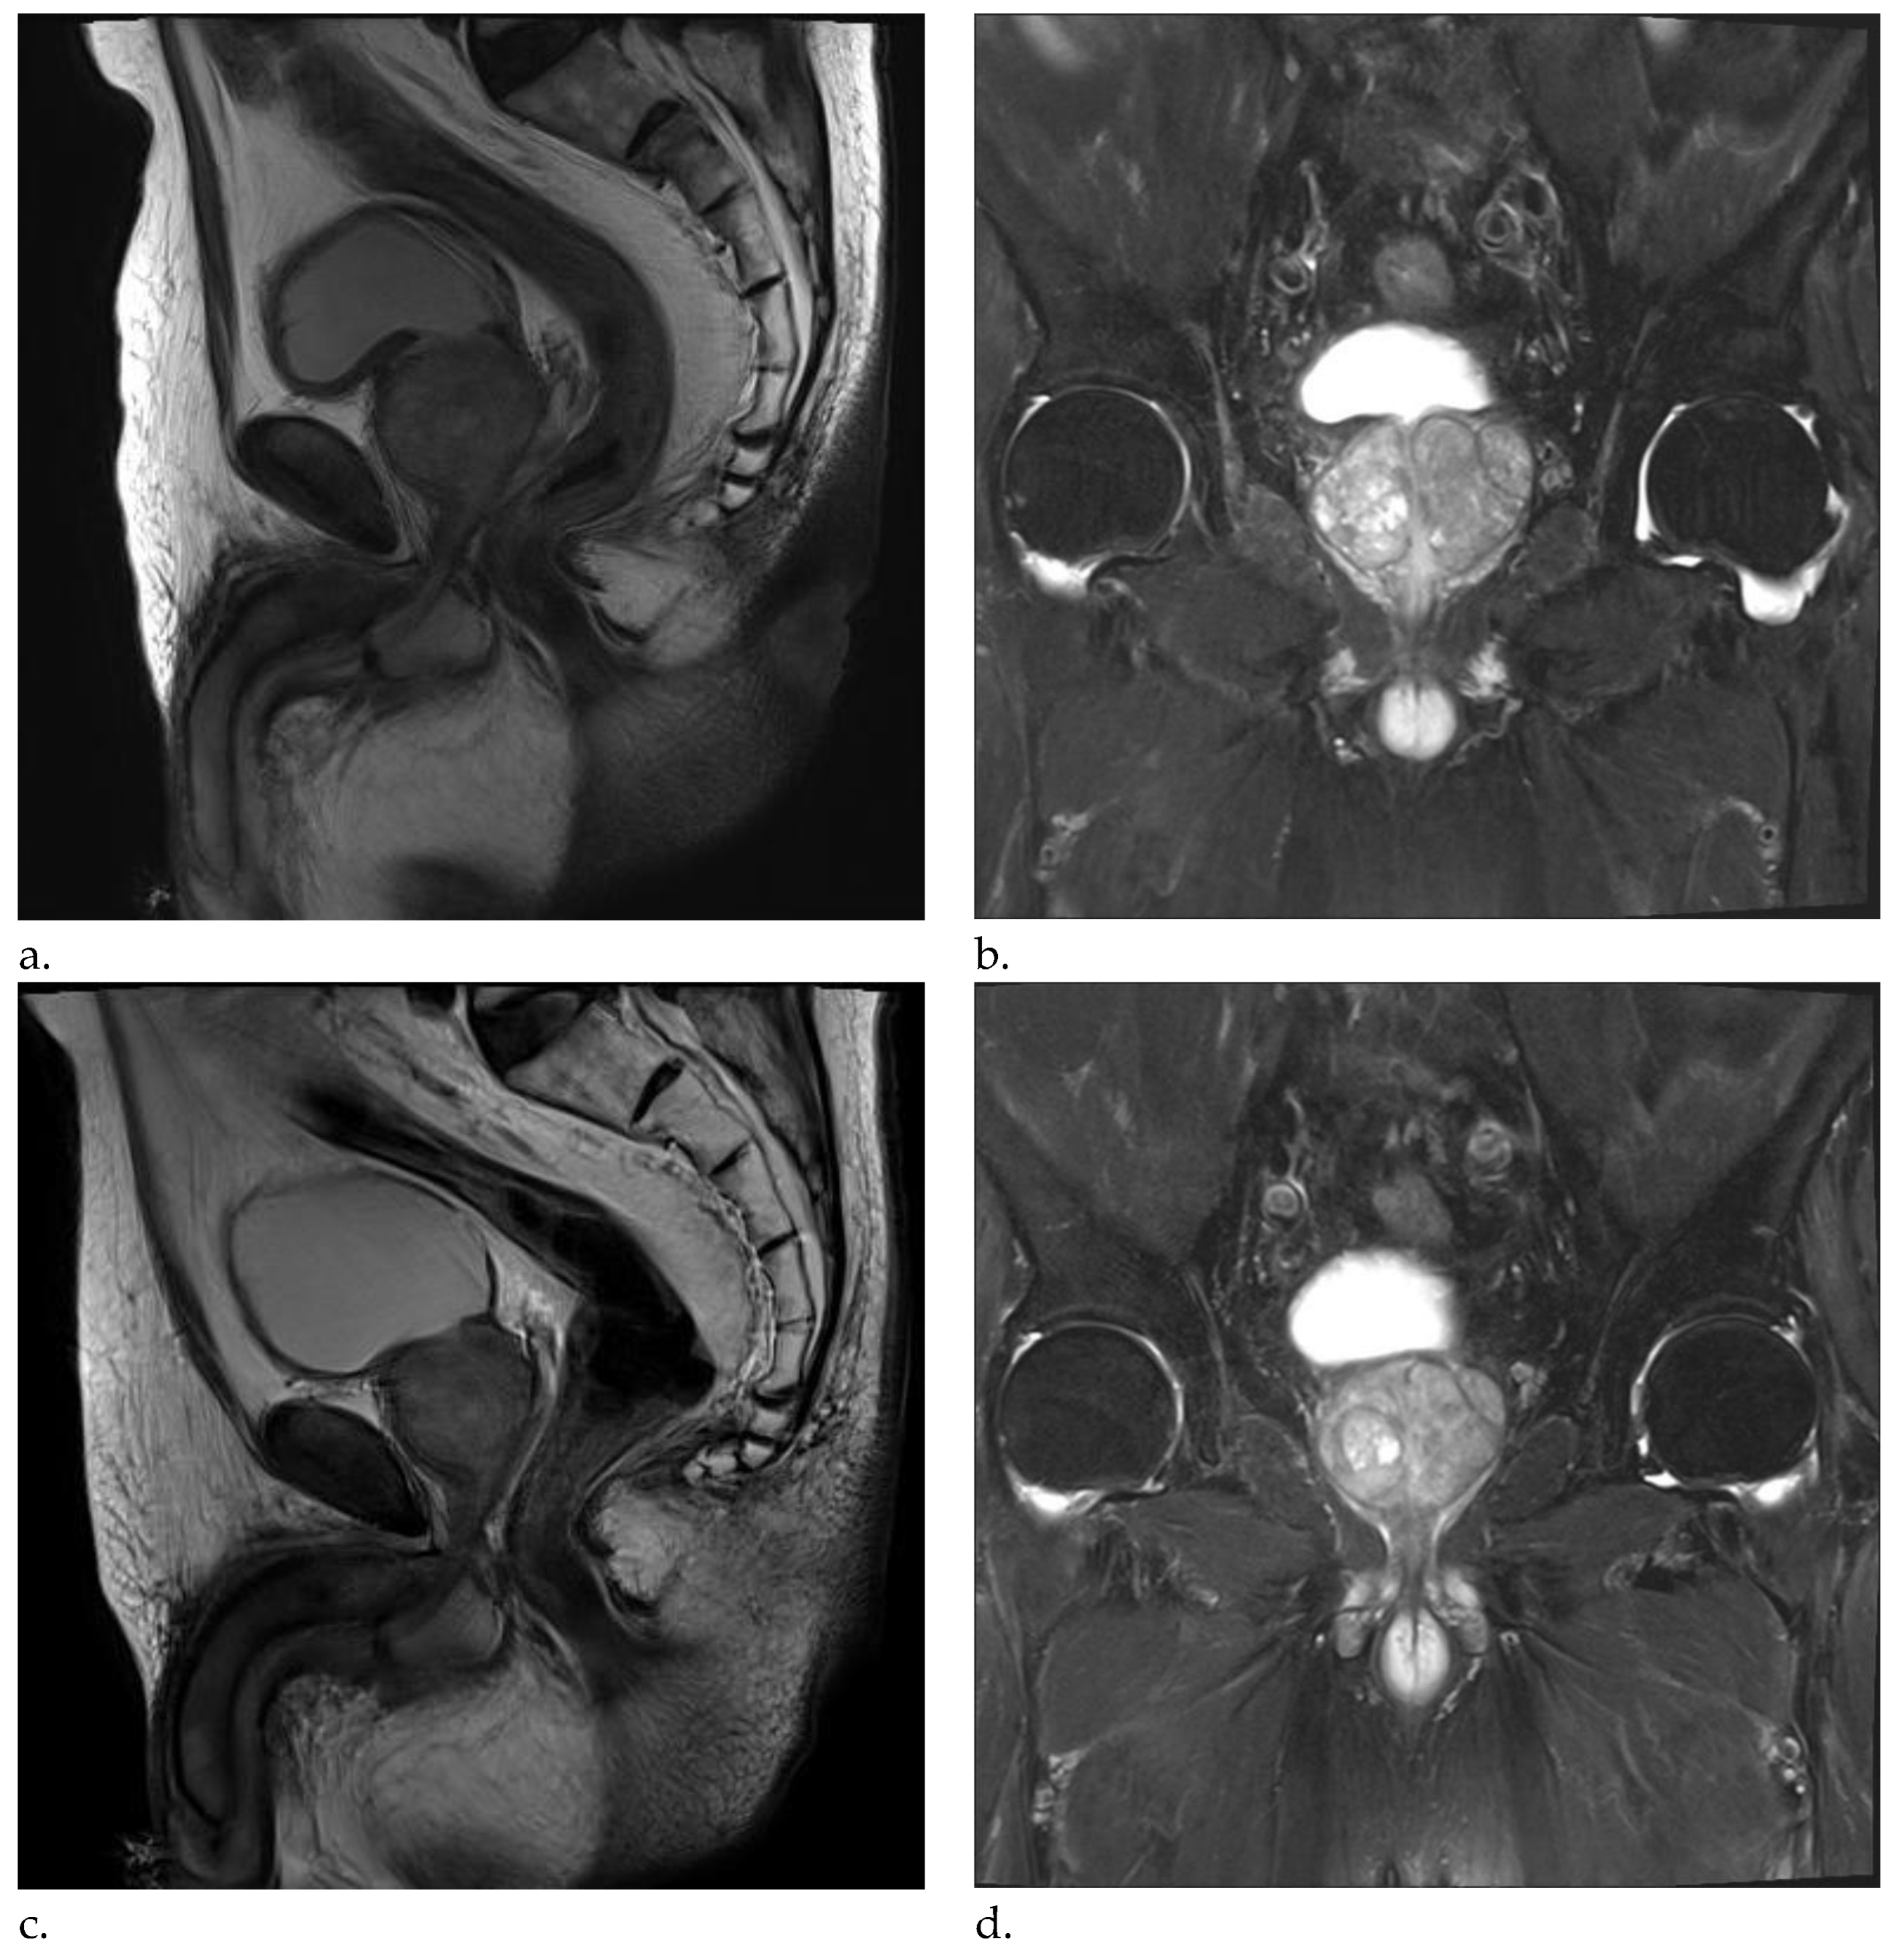

Pre-PAE MRI showed an enlarged prostate with central gland 89.39 cm3 (5.90cm x 4.41 cm x 3.84cm) (Figure 1a- b). After discussion with urologist, this patient was identified as a PAE candidate.

Patient was followed up at 1 week in the Department of Urology, significant improvement in symptom score was noted. Further improvement was found along the follow-ups with 78.3% at month 12 and a total of IPSS 18 points improvement. Quality of life (QoL) was improved significantly from 5 to 1 at week 1 and good through the last follow-up. 6-month MRI showed a significant prostate volume reduction of 20.3% and 12- & 24-month MRI with 28.6% and 35% reductions, respectively. (Figure 1 c-d) PSA dropped 47.3% from baseline to month 12. The post-void residual volume improved by 43.5% at 1-year follow-up from 155ml at baseline to 87.6ml. Patient stopped medical treatment at month 12 and no longer continue thereafter. No further hospitalization regarding BPH after PAE nor symptom recurrence for more than 3 years. Patient lived a normal life with minimal LUTS. Table 1 describes the clinical outcomes of this patient.

Figure 1. MRI images of patient’s BPH. (a-b) Pre-Procedural MRI showed enlarged prostate of 89.39 cm3 (5.90cm x 4.41 cm x 3.84cm). (c-d) Post-procedural MRI at 24-months showed 66.05 cm3 (4.92cm x 3.58 cm x 3.75cm).